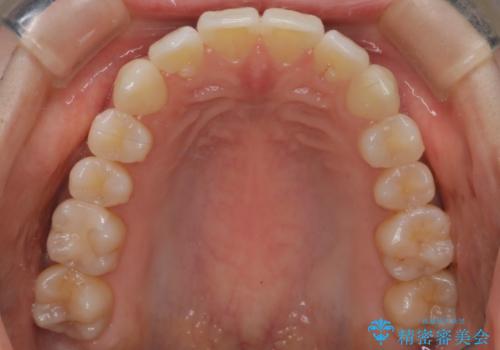

- インビザラインで非抜歯治療を行いました。IPRと拡大をし、叢生、咬合をきれいにしました。

主訴であったかみ合わせを正しい位置に動かし、バランスよくかめるようになりました。矯正治療終了後にメタルインレーをセラミックインレーに替えました。